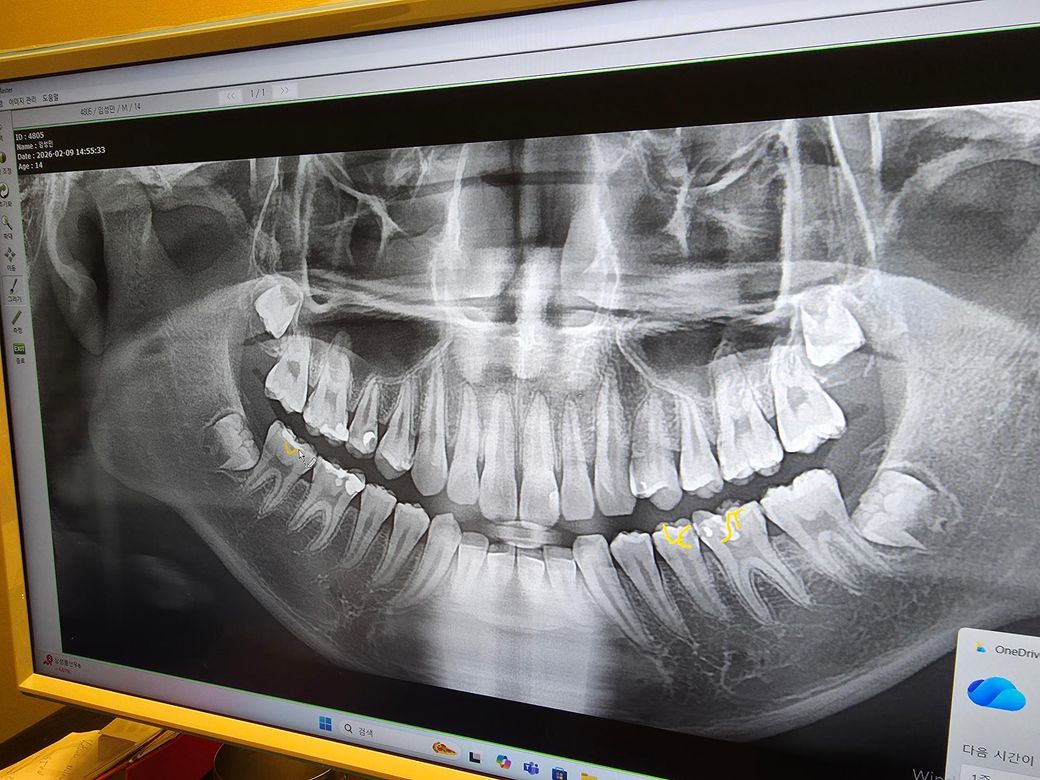

중3 아들의 치아 엑스레이 사진입니다

치과에서 15번 치아 크라운과 치질보강을 권장했습니다

치아상태를 보고 신경치료 하거나 신경치료 없이 크라운을 하자고합니다

궁금한건 15번 치아가 크라운을 꼭 해야되는 상태인가요

35번 36번 인레이 견적을 받았습니다

꼭 해야 될 상태인지 고견 부탁드립니다

현재 상태에서는 반드시 해야 하며 충치 범위가 굉장히 커 보입니다. 15번 치아는 단순히 크라운이 아닌 신경치료를 해야할 가능성도 매우 높아 보입니다. 또한 노란색으로 체크한 치아들도 제거 이후 인레이를 하더라도 시린 증상 등이 추가적으로 나타난다면 신경치료 가능성이 있습니다. 전체적으로 치아 사이의 인접면 충치가 많으므로 치료 비용이 꽤 많이 나오며 시간도 오래걸릴 것 같습니다.